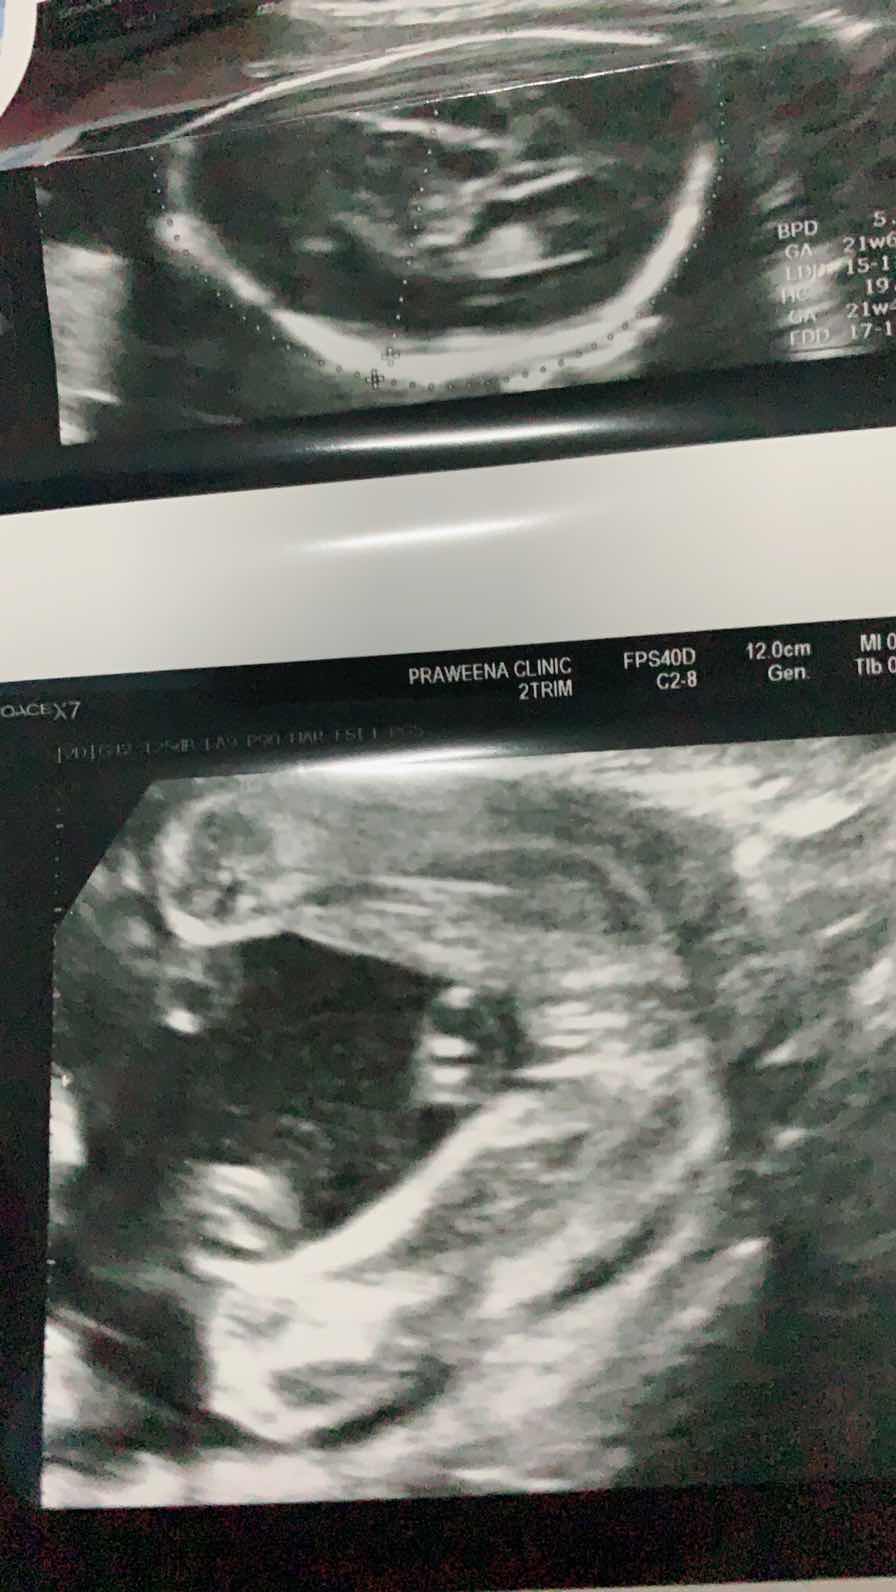

คุณแม่ท่านไหนคลอดเดือนพย.62มั้งค่ะขอเสียงหน่อย ได้ลูกสาวหรือลูกชายกันค่ะ ? บ้านนี้วันนี้พึ่งไปอัลตร้าซาวมาเป็นลูกสาวกำหนดคลอด21พย.ค่ะเห็นจิมิชัดมาก